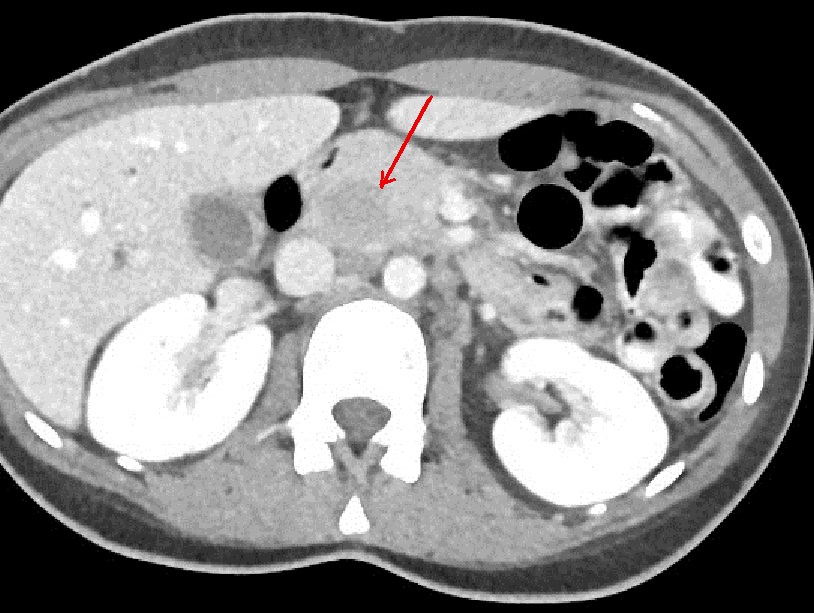

Meme cas en

coupe coronale |

Image radiologique TDM d'une

lymphome pancreatique a aspect lesionnel en forme

nodulaire hypodense , homogene situe au queu du

pancreas ( fleche rouge ) . |

|

En association de lymphome de

la

queue du pancreas on peut retruuver image des

adenopathies aspect hypodense ovalaire situe sous diapragmatique (

fleche rouge ) . Image radiologique TDM en coupe

axilaire |

Des adenopahthies de tumeur lymphoide

peut situe sous ou perihilaire renale ( fleche

rouge ) . Une caracteristique des lymphomes

pancreatiques est l'absence de envahissement

vasculaire et l'absence de metastase hepatique |